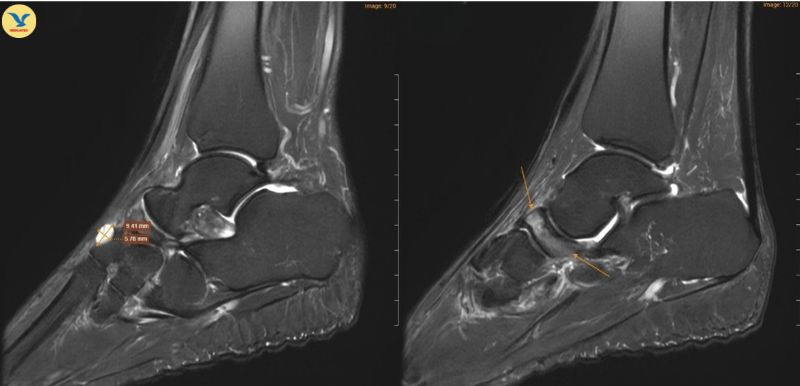

Hình ảnh chụp MRI cho thấy những dấu hiệu đặc trưng của Hội chứng Mueller-Weiss ở chân phải

Tại MEDLATEC, bác sĩ đã chỉ định chụp Cộng hưởng từ (MRI) để tìm kiếm những tổn thương sâu trong cấu trúc xương. Trên lát cắt Sagittal T1W, hình ảnh cho thấy xương ghe bị xẹp và biến dạng điển hình hình dấu phẩy, kèm theo tình trạng đặc xương dưới sụn. Trên chuỗi xung T2W FS, ghi nhận tình trạng phù tủy xương ghe rõ rệt.